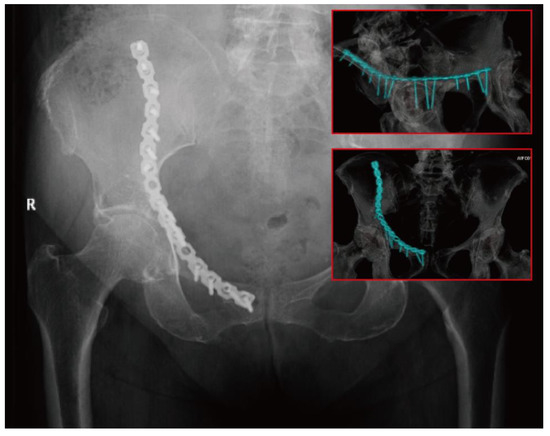

3.3. Different Models of Third-Generation DAPSQ Plate and Verification

| Models | Total Length | Pubic Region | Quadrilateral Region | Iliac Region | |

|---|---|---|---|---|---|

| Small size | A1 | 194 | 55 | 61 | 78 |

| A2 | 194 | 51 | 66 | 77 | |

| Medium size | B1 | 214 | 51 | 67 | 86 |

| B2 | 214 | 56 | 73 | 84 | |

| Large size | C1 | 234 | 66 | 74 | 94 |

| C2 | 234 | 62 | 80 | 92 | |